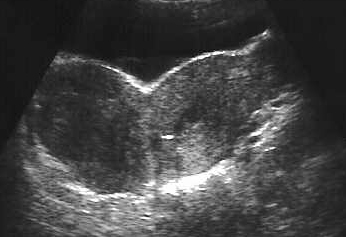

Utérus bicorne. Signe du V vésical